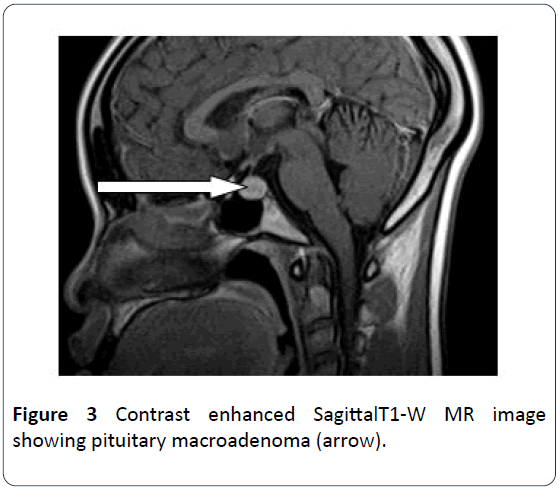

What is a Renin Test The renin test measures the amount of renin in the blood. Epidemiology Male Female. Magnetic resonance imaging MRI scan of pituitary macroadenoma. A prolactin test measures the amount of a hormone called prolactin you have in your blood. X-ray imaging tests including the pros and cons of each test how. They range between 4-23 ngmL mcgL in adult nonpregnant women and 3-15 ngmL in men 7 3.

If a pituitary mass is suspected MRI is the best initial imaging study7 MRI is 61 to 72 sensitive and 88 to 90 specific for sellar. MRI with contrast can generate highly detailed visuals of internal organs and soft tissues. Identification of the disorder becomes clearer as the pituitary reverts to its normal size and recovers some of its normal function. Functional adenomas can cause problems because of the hormones they release. Normal range by age in years BUN. In healthy normal individuals the hypothalamus just above the brainstem sends CRH or corticotrophin-releasing hormone to the pituitary gland located behind the nose.

A magnetic resonance imaging MRI scan may be ordered to look for evidence of a pituitary growth or for damage to surrounding tissues. The first signs of a pituitary adenoma often depend on whether the tumor is functional making excess hormones or non-functional not making excess hormones. If sufficient normal tissue is excised inadvertently symptomatic hypogonadism may ensue initially followed by dysfunction of other pituitary cells. Thus regulation of thyroid function in normal individuals is to a large extent determined by the factors which regulate the synthesis. Chances are VERY high that your Free T4 level isnt actually normal even though it may be in the normal range. Blood tests to evaluate other hormone levels may be useful in ruling out any other possible causes of the symptoms.